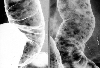

Diffuse Lymphoid Hyperplasia (case 1)

X-ray

Tumor-like lesions/Benign lymphoid polyposis